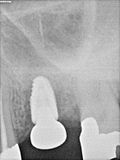

fredlibc | all galleries >> Galleries >> JLin - 26 implant -graft around existing 36 impl > R3.jpg